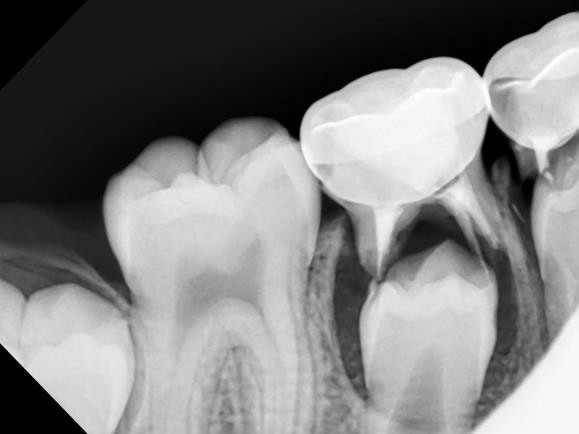

A new paper in Science Advances describes for the first time how minerals come together at the molecular level to form bones and other hard tissues, like teeth and enamel.

The University of Illinois Chicago researchers who published the paper described their experiments -- which captured high-resolution, real-time images of the mineralization process in an artificial saliva model -- and their discovery of distinct pathways that support bone and teeth formation, or biomineralization.

Shahbazian-Yasser and his colleagues observed that both direct and indirect formations of hydroxyapatite crystals -- the foundation of hard tissues -- can be achieved by local variations in energetic pathways for nucleation and growth.

"The control over the dissolution of amorphous calcium phosphate affects the assembly of hydroxyapatite crystals into larger aggregates," Shahbazian-Yasser said. "Using technology developed at UIC, we found evidence that these pathways coexist simultaneously -- explaining why different groups had reported seemingly different or opposite results. In addition, we now understood how hydroxyapatite materials nucleate and grow on amorphous calcium phosphate templates. The control over the nucleation and growth of hydroxyapatite will aid in developing new drugs and medical treatments to heal lost or broken bone faster or cure tooth cavities."

To capture the images, the researchers used a unique micro-device that made it possible to use electron microscopy with a liquid model. Using this method, the researchers were able to monitor chemical reactions in the model on the smallest scale.